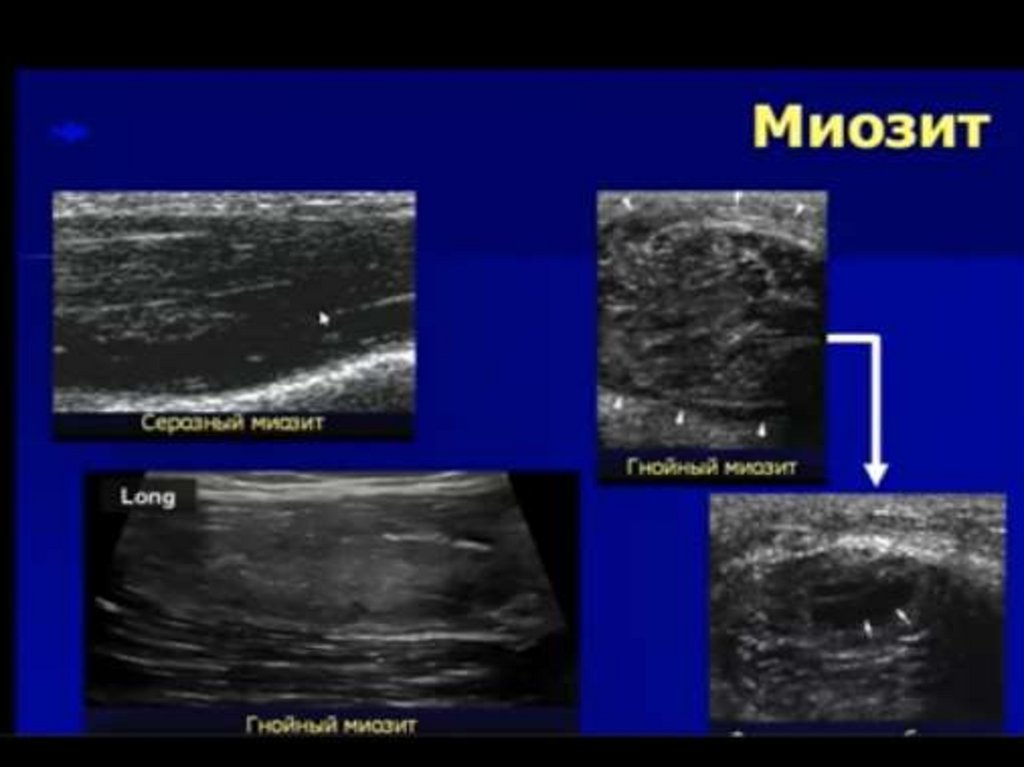

Ультразвуковая диагностика опорно-двигательного аппарата

Ультразвуковая диагностика

опорно-двигательного

аппарата